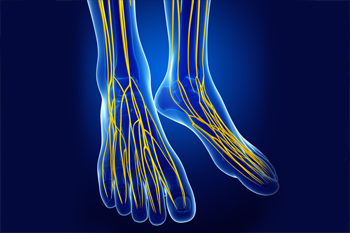

Exercise Can Benefit Patients With Peripheral Neuropathy

Peripheral neuropathy, which can cause weakness, numbness, and pain in your feet, might make you reluctant to exercise. However, there is scientific evidence that you can benefit from physical activity. Researchers have found that exercising can improve balance, strength, and walking speed, reduce neuropathic pain and sensory disturbances, and improve mobility and confidence in patients with peripheral neuropathy. Doctors recommend that patients with peripheral neuropathy engage in flexibility, endurance, strength, and balance exercises to get maximum results. A podiatrist can help you maintain an active and healthy lifestyle by providing treatments to slow the progression of the disease, decrease your pain, and maintain the health of your feet.

Peripheral neuropathy, which can cause weakness, numbness, and pain in your feet, might make you reluctant to exercise. However, there is scientific evidence that you can benefit from physical activity. Researchers have found that exercising can improve balance, strength, and walking speed, reduce neuropathic pain and sensory disturbances, and improve mobility and confidence in patients with peripheral neuropathy. Doctors recommend that patients with peripheral neuropathy engage in flexibility, endurance, strength, and balance exercises to get maximum results. A podiatrist can help you maintain an active and healthy lifestyle by providing treatments to slow the progression of the disease, decrease your pain, and maintain the health of your feet.

Neuropathy

What Is Neuropathy?

Neuropathy is a condition that leads to damage to the nerves in the body. Peripheral neuropathy, or neuropathy that affects your peripheral nervous system, usually occurs in the feet. Neuropathy can be triggered by a number of different causes. Such causes include diabetes, infections, cancers, disorders, and toxic substances.

Symptoms of Neuropathy Include:

- Numbness

- Sensation loss

- Prickling and tingling sensations

- Throbbing, freezing, burning pains

- Muscle weakness

Those with diabetes are at serious risk due to being unable to feel an ulcer on their feet. Diabetics usually also suffer from poor blood circulation. This can lead to the wound not healing, infections occurring, and the limb may have to be amputated.

Neuropathy is a condition in which the nerves in the body become damaged from a number of different illnesses. Nerves from any part of the body, including the foot, can be damaged. There are several forms of neuropathy including peripheral neuropathy, cranial neuropathy, focal neuropathy, and autonomic neuropathy. Furthermore there is also mononeuropathy and polyneuropathy. Mononeuropathies affect one nerve while polyneuropathies affect several nerves. Causes of neuropathy include physical injury, diseases, cancers, infections, diabetes, toxic substances, and disorders. It is peripheral neuropathy that affects the feet.

The symptoms of neuropathy vary greatly and can be minor such as numbness, sensation loss, prickling, and tingling sensations. More painful symptoms include throbbing, burning, freezing, and sharp pains. The most severe symptoms can be muscle weakness/paralysis, problems with coordination, and falling.